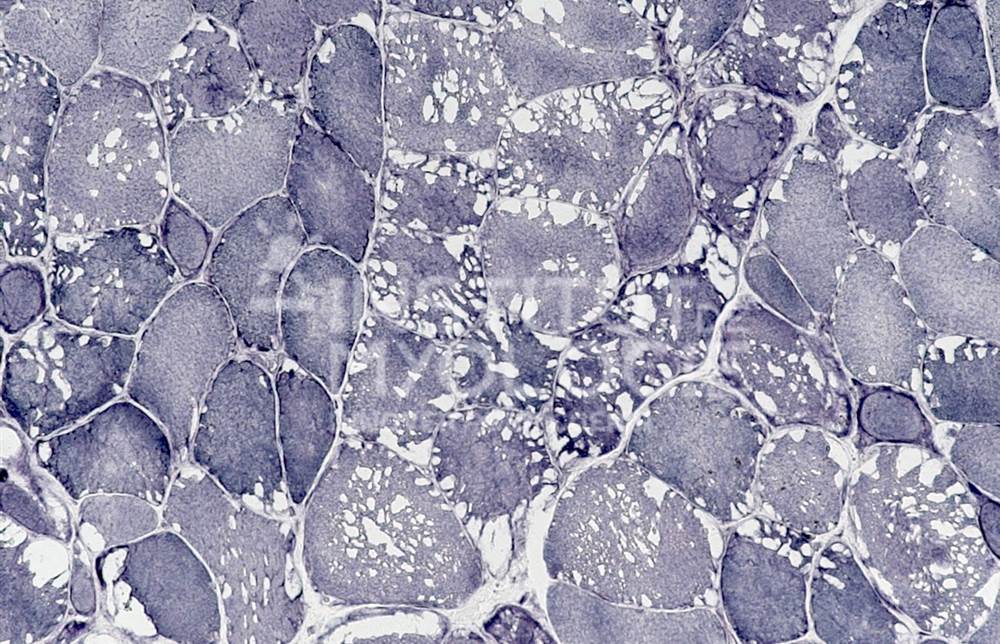

Welcome to the Muscle Atlas, the first database of muscle images designed to facilitate research, diagnosis and knowledge in the field of neuromuscular pathologies. Our vast collection includes more than 6,416 images of muscle biopsies from patients with various diseases and animal models, which may or may not be undergoing treatment. Each image is characterised according to the specific condition and corresponding stage of the disease.